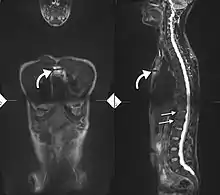

Imaging

X-rays

The earliest changes demonstrable by plain X-ray shows erosions and sclerosis in sacroiliac joints. Progression of the erosions leads to widening of the joint space and bony sclerosis. X-ray spine can reveal squaring of vertebrae with bony spur formation called syndesmophyte. This causes the bamboo spine appearance. A drawback of X-ray diagnosis is the signs and symptoms of AS have usually been established as long as 7–10 years prior to X-ray-evident changes occurring on a plain film X-ray, which means a delay of as long as 10 years before adequate therapies can be introduced.[24]

Options for earlier diagnosis are tomography and MRI of the sacroiliac joints, but the reliability of these tests is still unclear.

Lateral X-ray of the mid back in ankylosing spondylitis

Lateral X-ray of the neck in ankylosing spondylitis

X-ray showing bamboo spine in a person with ankylosing spondylitis

CT scan showing bamboo spine in ankylosing spondylitis

T1-weighted MRI with fat suppression after administration of gadolinium contrast showing sacroiliitis in a person with ankylosing spondylitis